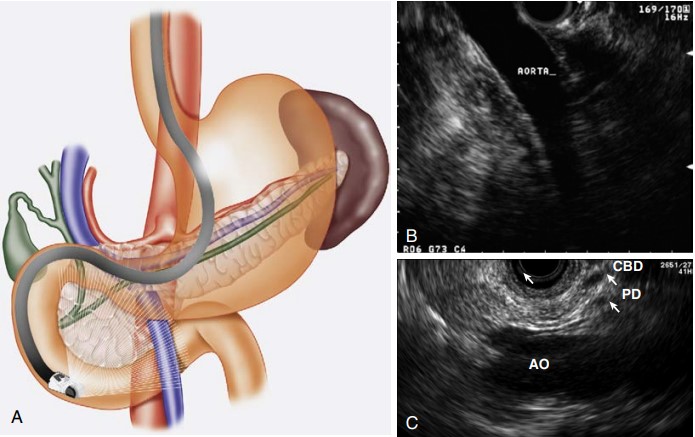

Investigating Biliary Tract Disorders

When it comes to biliary tract diseases, including gallstones and bile duct cancers, EUS plays a crucial role:

- Detecting Cholelithiasis: EUS can identify gallstones, especially small ones that might be missed by other imaging techniques.

- Evaluating Bile Duct Abnormalities: Assessing strictures and masses in the bile duct, crucial for appropriate intervention.